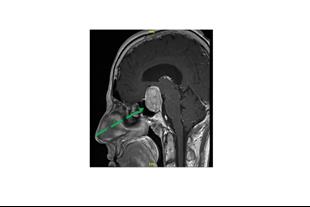

פרופ' גרוסמן מחזיקה בניסיון רב בניתוחים מיקרוכירורגיים מורכבים להסרת גידולים מוחיים שפירים וממאירים ניתוחים להסרת גליומות אינסולריות וניתוחים בעירות (awake craniotomy) לכריתת גידולים הממוקמים בסמיכות לאזורי שפה ותנועה ושימור תפקודים קוגניטיבים גבוהים וגרורות מוחיות. פרופ' גרוסמן בעלת ניסיון רב בניתוחים אנדוסקופיים להסרת גידולי היפופיזה (בלוטת יותרת המוח) והסרת גידולי מוחיים כגון מנינגיומות הממוקמים בבסיס הגולגולת.

• ניתוחים אנדוסקופיים (טרנס-ספנוידל) לכריתת גידולים של בלוטת יותרת המוח ובסיס הגולגולת (כולל מנינגיומות)